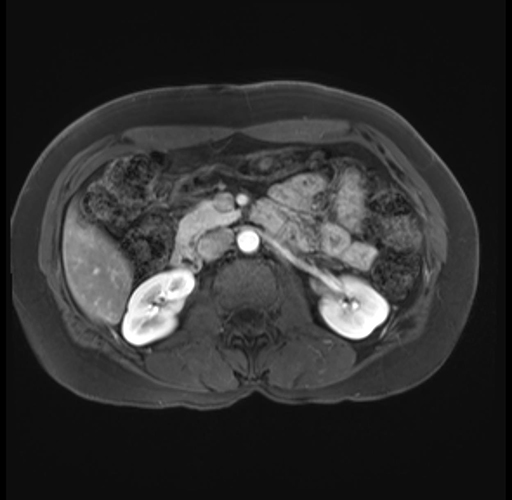

Imaging Analysis

Look through the patient's CT scan to identify any areas of concern for the necessary procedure.

Based on your CT findings, which issue(s) are present and would give reason for "planned slowing down moment(s)" in this case?